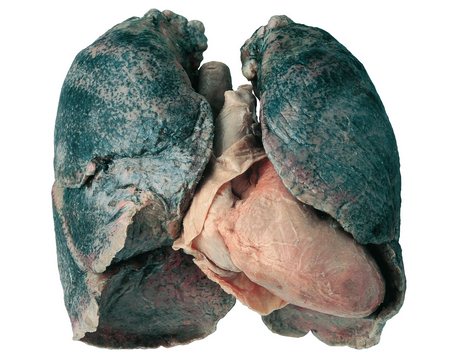

Как уже было сказано выше, легкие – это главный орган, на который воздействует саркоидоз. Лечение легких затрудненно по причине того, что в 90% случаев заболевание протекает абсолютно без каких бы то ни было выраженных симптомов. В подобных ситуациях саркоидоз можно выявить только при рентгенологическом исследовании. Отсутствие симптомов объясняется поражением внутрилегочных лимфаузлов, что в подавляющем большинстве случаев можно определить только с помощью специальной аппаратуры, так как у больных не наблюдается никаких внешних проявлений.

- фиброза легких и ухудшения нормального функционирования органов дыхательной системы.

Кроме того, саркоидоз легких обнаруживает себя воспалительными изменениями на коже, в лифматических узлах и суставах. Отсутствие адекватного лечения может привести к полной слепоте человека и необратимым изменениям в мозге, сердце, почках и печени.

Состояние легочных тканей и распространение воспаления контролируются с помощью регулярных рентгенологических исследований.